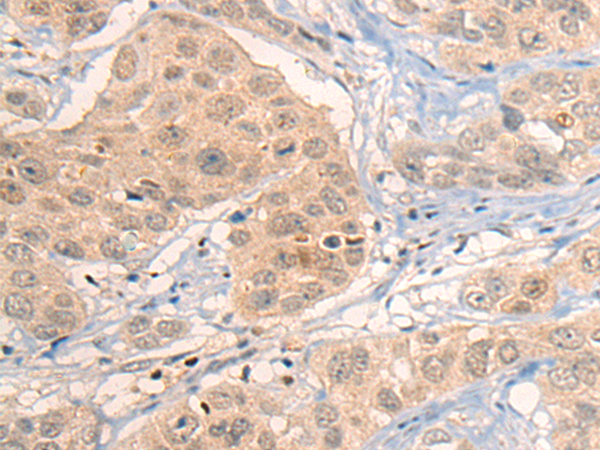

分类: 科研抗体货号: P13149别名: HB1; HB2; HH1; IVF; VF1; HBBD; ICCD; LQT3; SSS1; CDCD2; CMD1E; CMPD2; PFHB1; Nav1.5应用: IHC反应种属: Human, Mouse, Rat